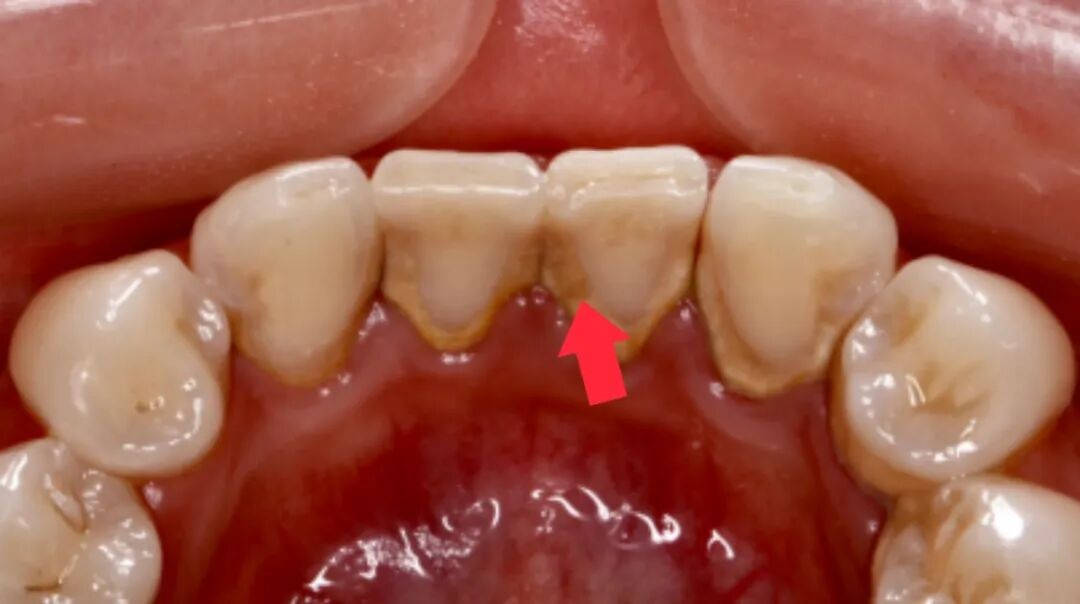

牙龈健康的恢复:炎症消退

如果在治疗前,你的牙龈因为炎症而肿胀,这种肿胀会暂时“遮住”一部分牙缝。在治疗后,随着炎症消退,牙龈会恢复到健康状态并贴合在牙齿表面,这时牙缝也会显得更加明显。

治疗前

治疗后